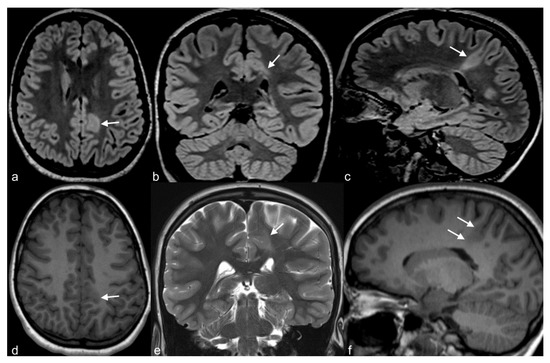

Figure 4.

36-year-old woman. The right hippocampus is smaller than the left (arrows) as seen on coronal T2WI (a), FLAIR (b) and MP2RAGE (c) and shows hyperintensity on T2WI and FLAIR. There is also flattening and loss of the normal undulations of the right hippocampus, suggestive of hippocampal sclerosis.